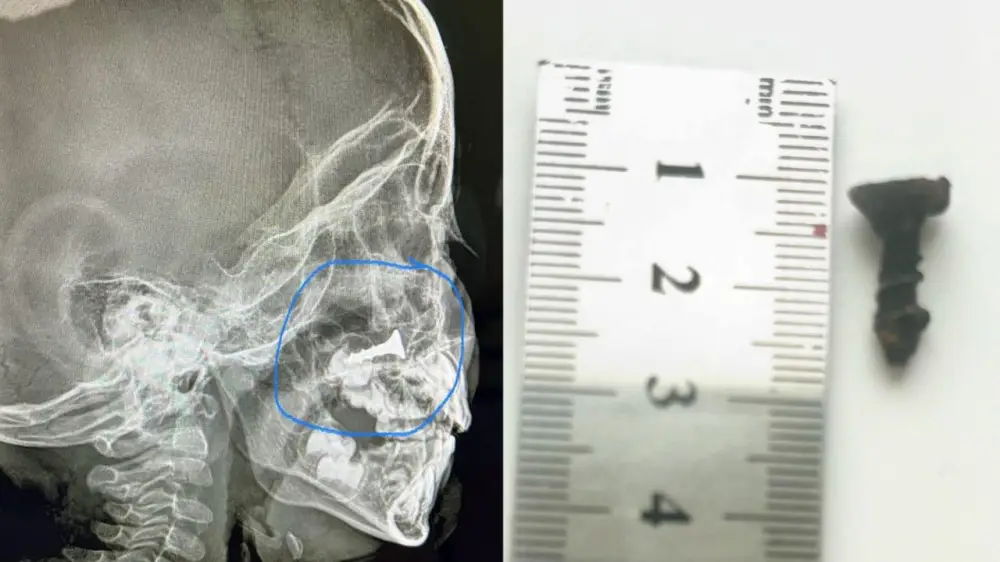

"Снимок показал наличие шурупа в носу малыша. Размер его - два сантиметра. Он находился там около полугода, но шуруп никак не беспокоил мальчика, поэтому родители не обращались за медицинской помощью. А на днях его мама решила провести рентген-обследование своему ребенку. Там-то все и обнаружилось. Сразу же малыш был госпитализирован в отделение, ему проведена операция под общим наркозом. Инородное тело успешно извлечено. Операцию провел молодой лор-врач Айбол Конысбаев. Ребенок чувствует себя хорошо", - сказал он.

Фото предоставлено врачами многопрофильной детской больницы Кызылорды